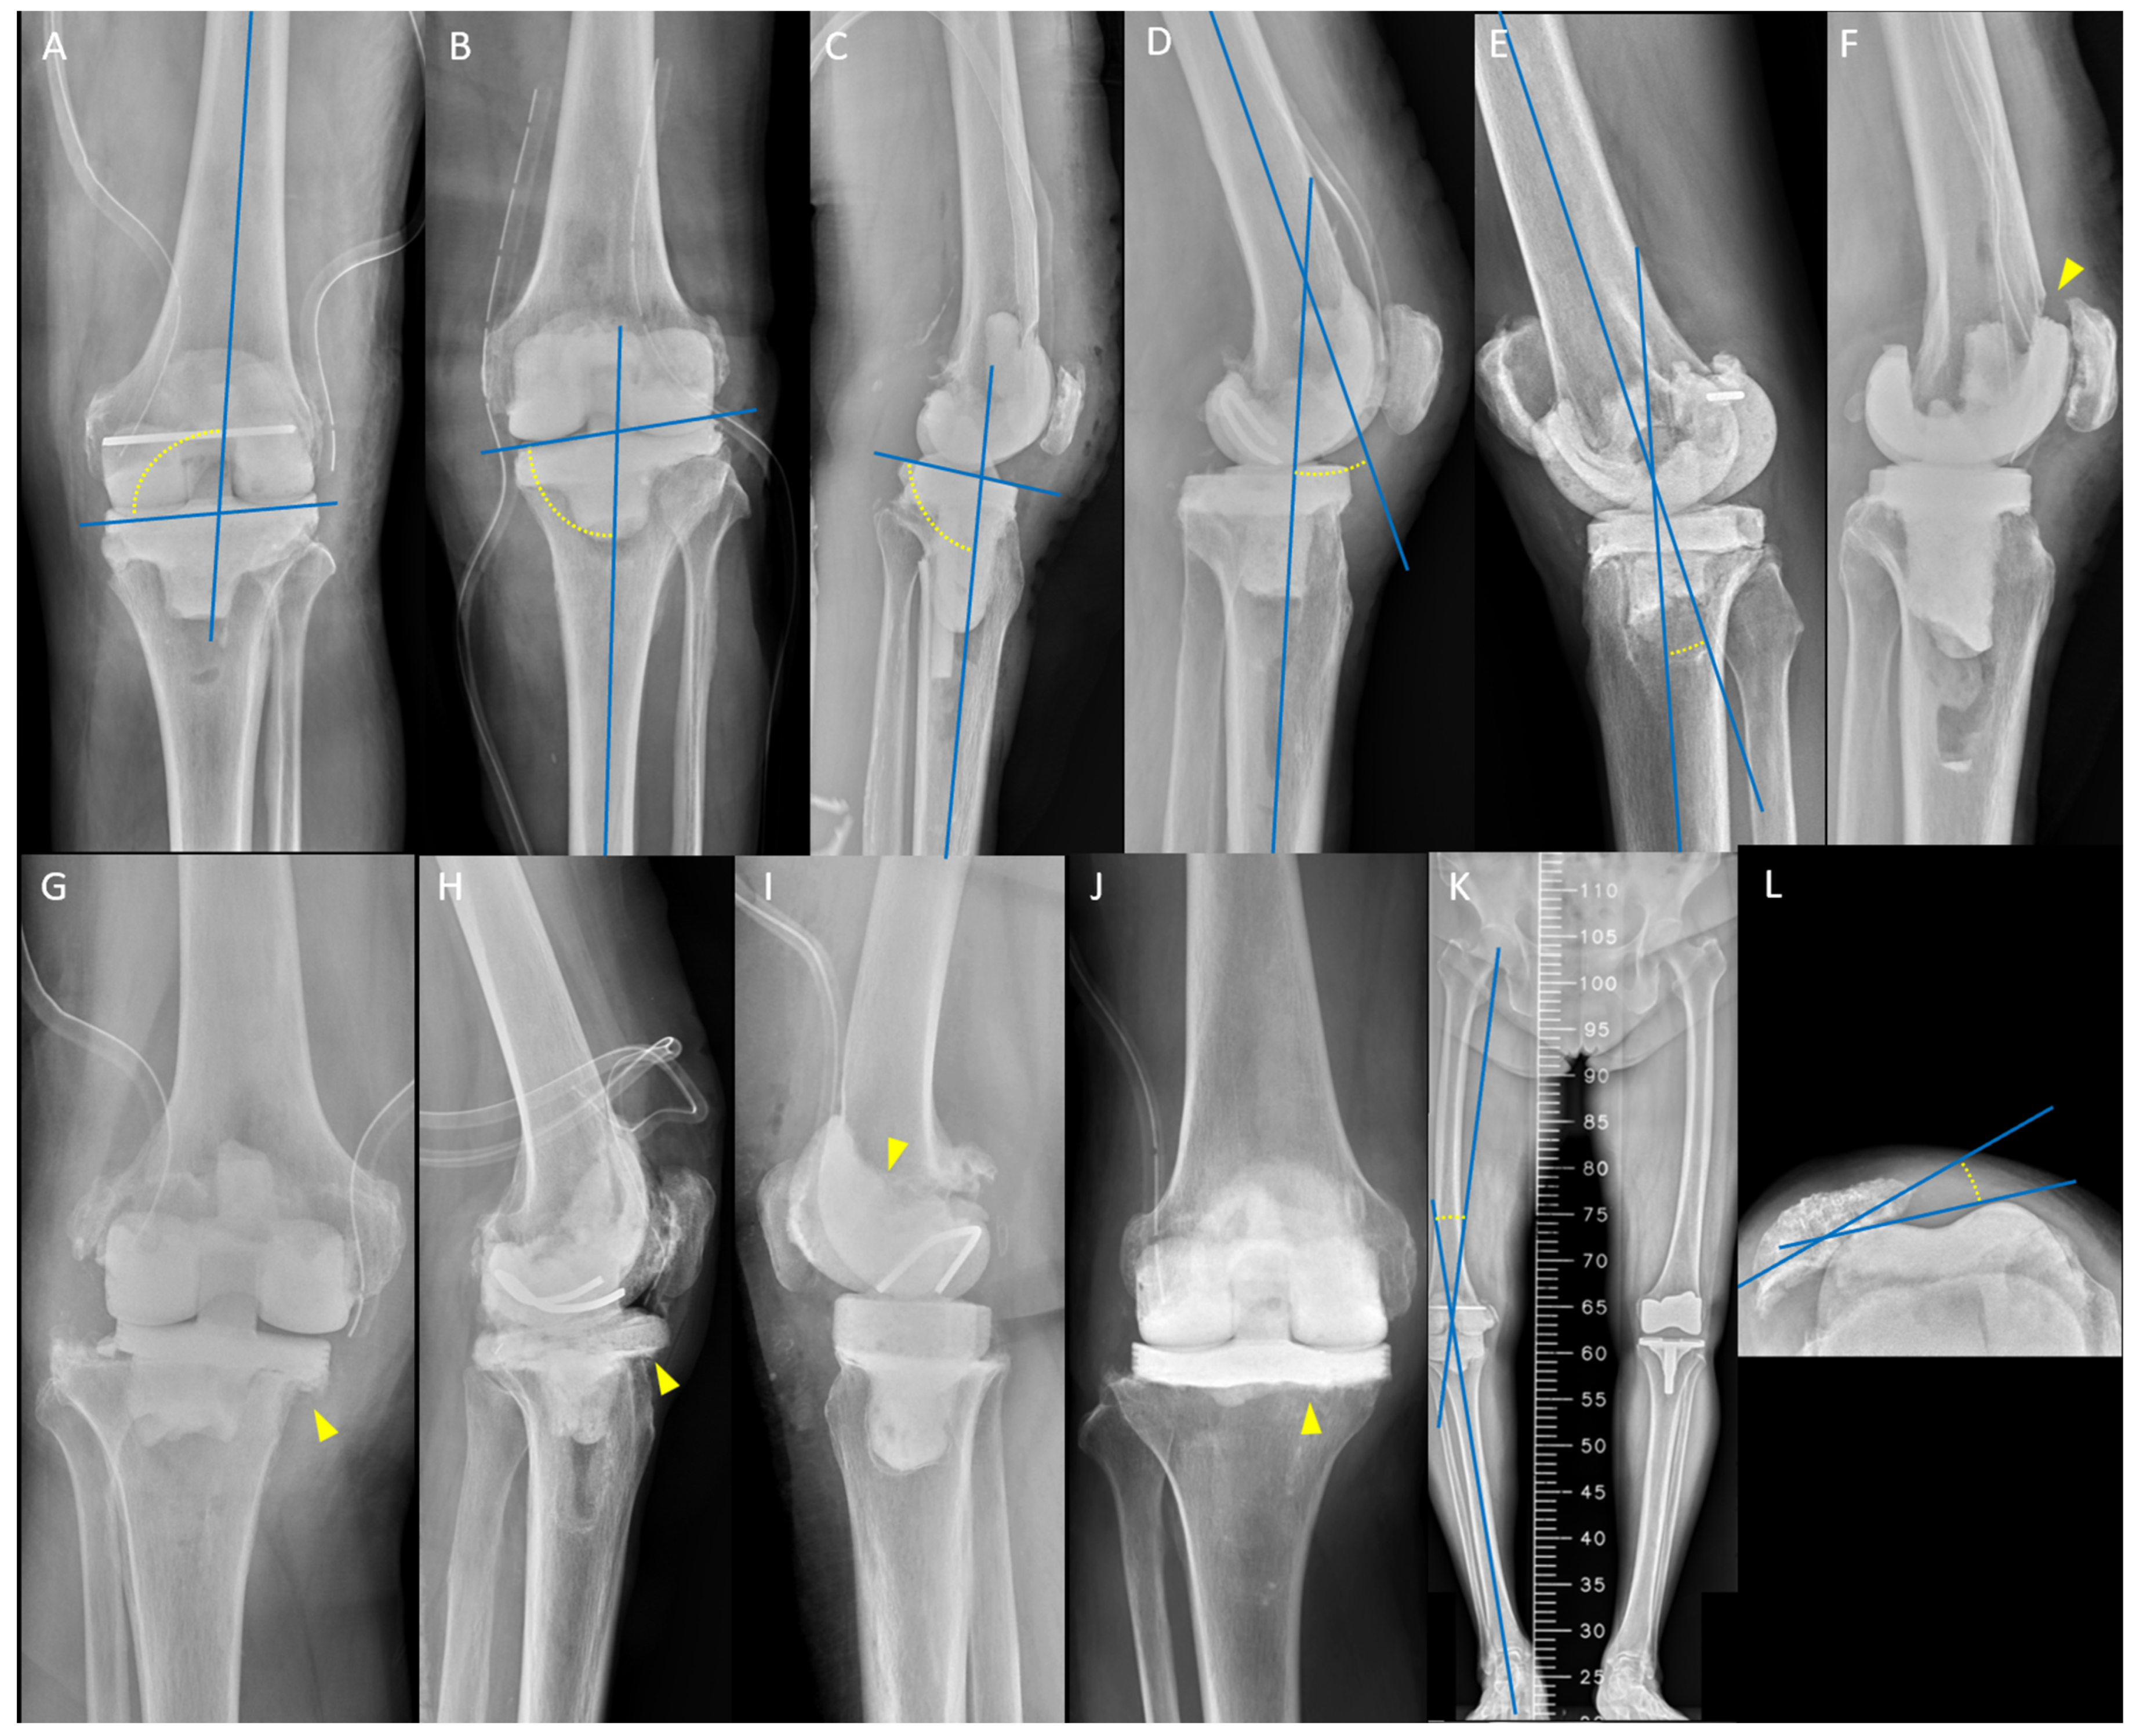

| Patient No. | Age (Years) | Sex | Radiographic Outlier | Mechanical Complication | Timing after Spacer (Weeks) | Intervention |

|---|---|---|---|---|---|---|

| HV surgeons | ||||||

| 1 | 69 | F | PTA < 87°; HKA < −10° | TS migration | 3 | Hinge knee brace |

| 2 | 64 | M | TS overhang; DFA > 98° | TS fracture | 4 | Hinge knee brace |

| 3 | 76 | M | PTA > 90°; FS notching | TS fracture | 5 | Both spacers exchange |

| 4 | 77 | F | Recurvatum deformity | Joint dislocation | 6 | Unexpected early reimplantation |

| LV surgeons | ||||||

| 1 | 73 | M | PTA < 87°; DFA < 92° | TS fracture | 2 | Hinge knee brace |

| 2 | 66 | M | PTA < 87°; DFA > 98° | Joint subluxation | 5 | Hinge knee brace |

| 3 | 82 | M | PTA < 87°; FS notching | Joint subluxation | 4 | Hinge knee brace |

| 4 | 63 | F | PTA < 87°; patellar maltracking | Joint dislocation | 4 | Open reduction |

| 5 | 66 | F | PTA < 87°; HKA < −10° | Joint subluxation | 3 | TS exchange |

| 6 | 86 | F | PTA < 87°; flexion contracture | Joint dislocation | 6 | TS exchange |

| 7 | 77 | F | PTA < 87° | Joint dislocation | 4 | TS exchange |

| 8 | 71 | M | PTA < 87°; FS without cement stem extension | Joint dislocation | 5 | TS exchange |

| 9 | 68 | M | PTA < 87° | Periprosthetic tibial fracture | 3 | TS exchange |

| 10 | 73 | M | PTA < 87°; flexion contracture | Periprosthetic tibial fracture | 4 | Both spacers exchange |

| 11 | 72 | F | PTA < 87°; HKA < −10° | Both spacers fracture | 6 | Unexpected early reimplantation |

| 12 | 68 | F | Recurvatum deformity; DFA > 98° | Joint subluxation | 5 | Hinge knee brace |

| 13 | 58 | M | Recurvatum deformity | Joint subluxation | 7 | Hinge knee brace |

| 14 | 72 | M | Recurvatum deformity; TS without cement stem extension | Joint dislocation | 4 | Both spacers exchange |

| 15 | 80 | F | Recurvatum deformity; TS overhang | Joint dislocation | 6 | Both spacers exchange |

| 16 | 66 | F | Recurvatum deformity; HKA angle < −10° | Joint dislocation | 7 | FS exchange |

| 17 | 60 | M | Recurvatum deformity; DFA < 92° | Joint dislocation | 4 | FS exchange |

| 18 | 80 | F | Recurvatum deformity; patellar maltracking | Joint dislocation | 8 | FS exchange |

| 19 | 67 | F | Recurvatum deformity; FS notching | Joint dislocation | 4 | FS exchange |

| 20 | 63 | M | Recurvatum deformity | FS fracture | 4 | Both spacers exchange |

| 21 | 60 | M | Recurvatum deformity; FS without cement stem extension | Periprosthetic tibial fracture | 6 | Unexpected early reimplantation |

| 22 | 61 | M | TS without cement stem extension | Joint subluxation | 4 | Hinge knee brace |

| 23 | 73 | F | TS without cement stem extension; DFA > 98° | Joint subluxation | 5 | Hinge knee brace |

| 24 | 61 | M | TS without cement stem extension | Joint dislocation | 3 | Both spacers exchange |

| 25 | 72 | M | TS without cement stem extension; DFA < 92° | Joint dislocation | 6 | Both spacers exchange |

| 26 | 75 | F | TS without cement stem extension; patellar maltracking | TS migration | 3 | TS exchange |

| 27 | 68 | F | TS without cement stem extension | TS migration | 4 | TS exchange |

| 28 | 69 | M | TS without cement stem extension; PSA > 90° | TS migration | 4 | Both spacers exchange |

| 29 | 73 | F | TS without cement stem extension; TS overhang | TS migration | 3 | TS exchange |

| 30 | 60 | F | TS without cement stem extension; HKA angle < −10° | TS migration | 5 | TS exchange |

| 31 | 66 | M | TS without cement stem extension; PTA > 93° | TS migration | 3 | TS exchange |

| 32 | 76 | F | TS without cement stem extension | TS migration | 6 | Unexpected early reimplantation |

| 33 | 77 | F | TS overhang; DFA > 98° | Extensor mechanism disruption | 3 | TS exchange |

| 34 | 67 | M | Patellar maltracking; DFA < 92° | Extensor mechanism disruption | 4 | Lateral release |

| 35 | 64 | F | HKA < −10°; DFA < 92° | TS migration | 6 | Unexpected early reimplantation |

| 36 | 72 | F | HKA < −10°; flexion contracture | Both spacers fracture | 3 | Hinge knee brace |